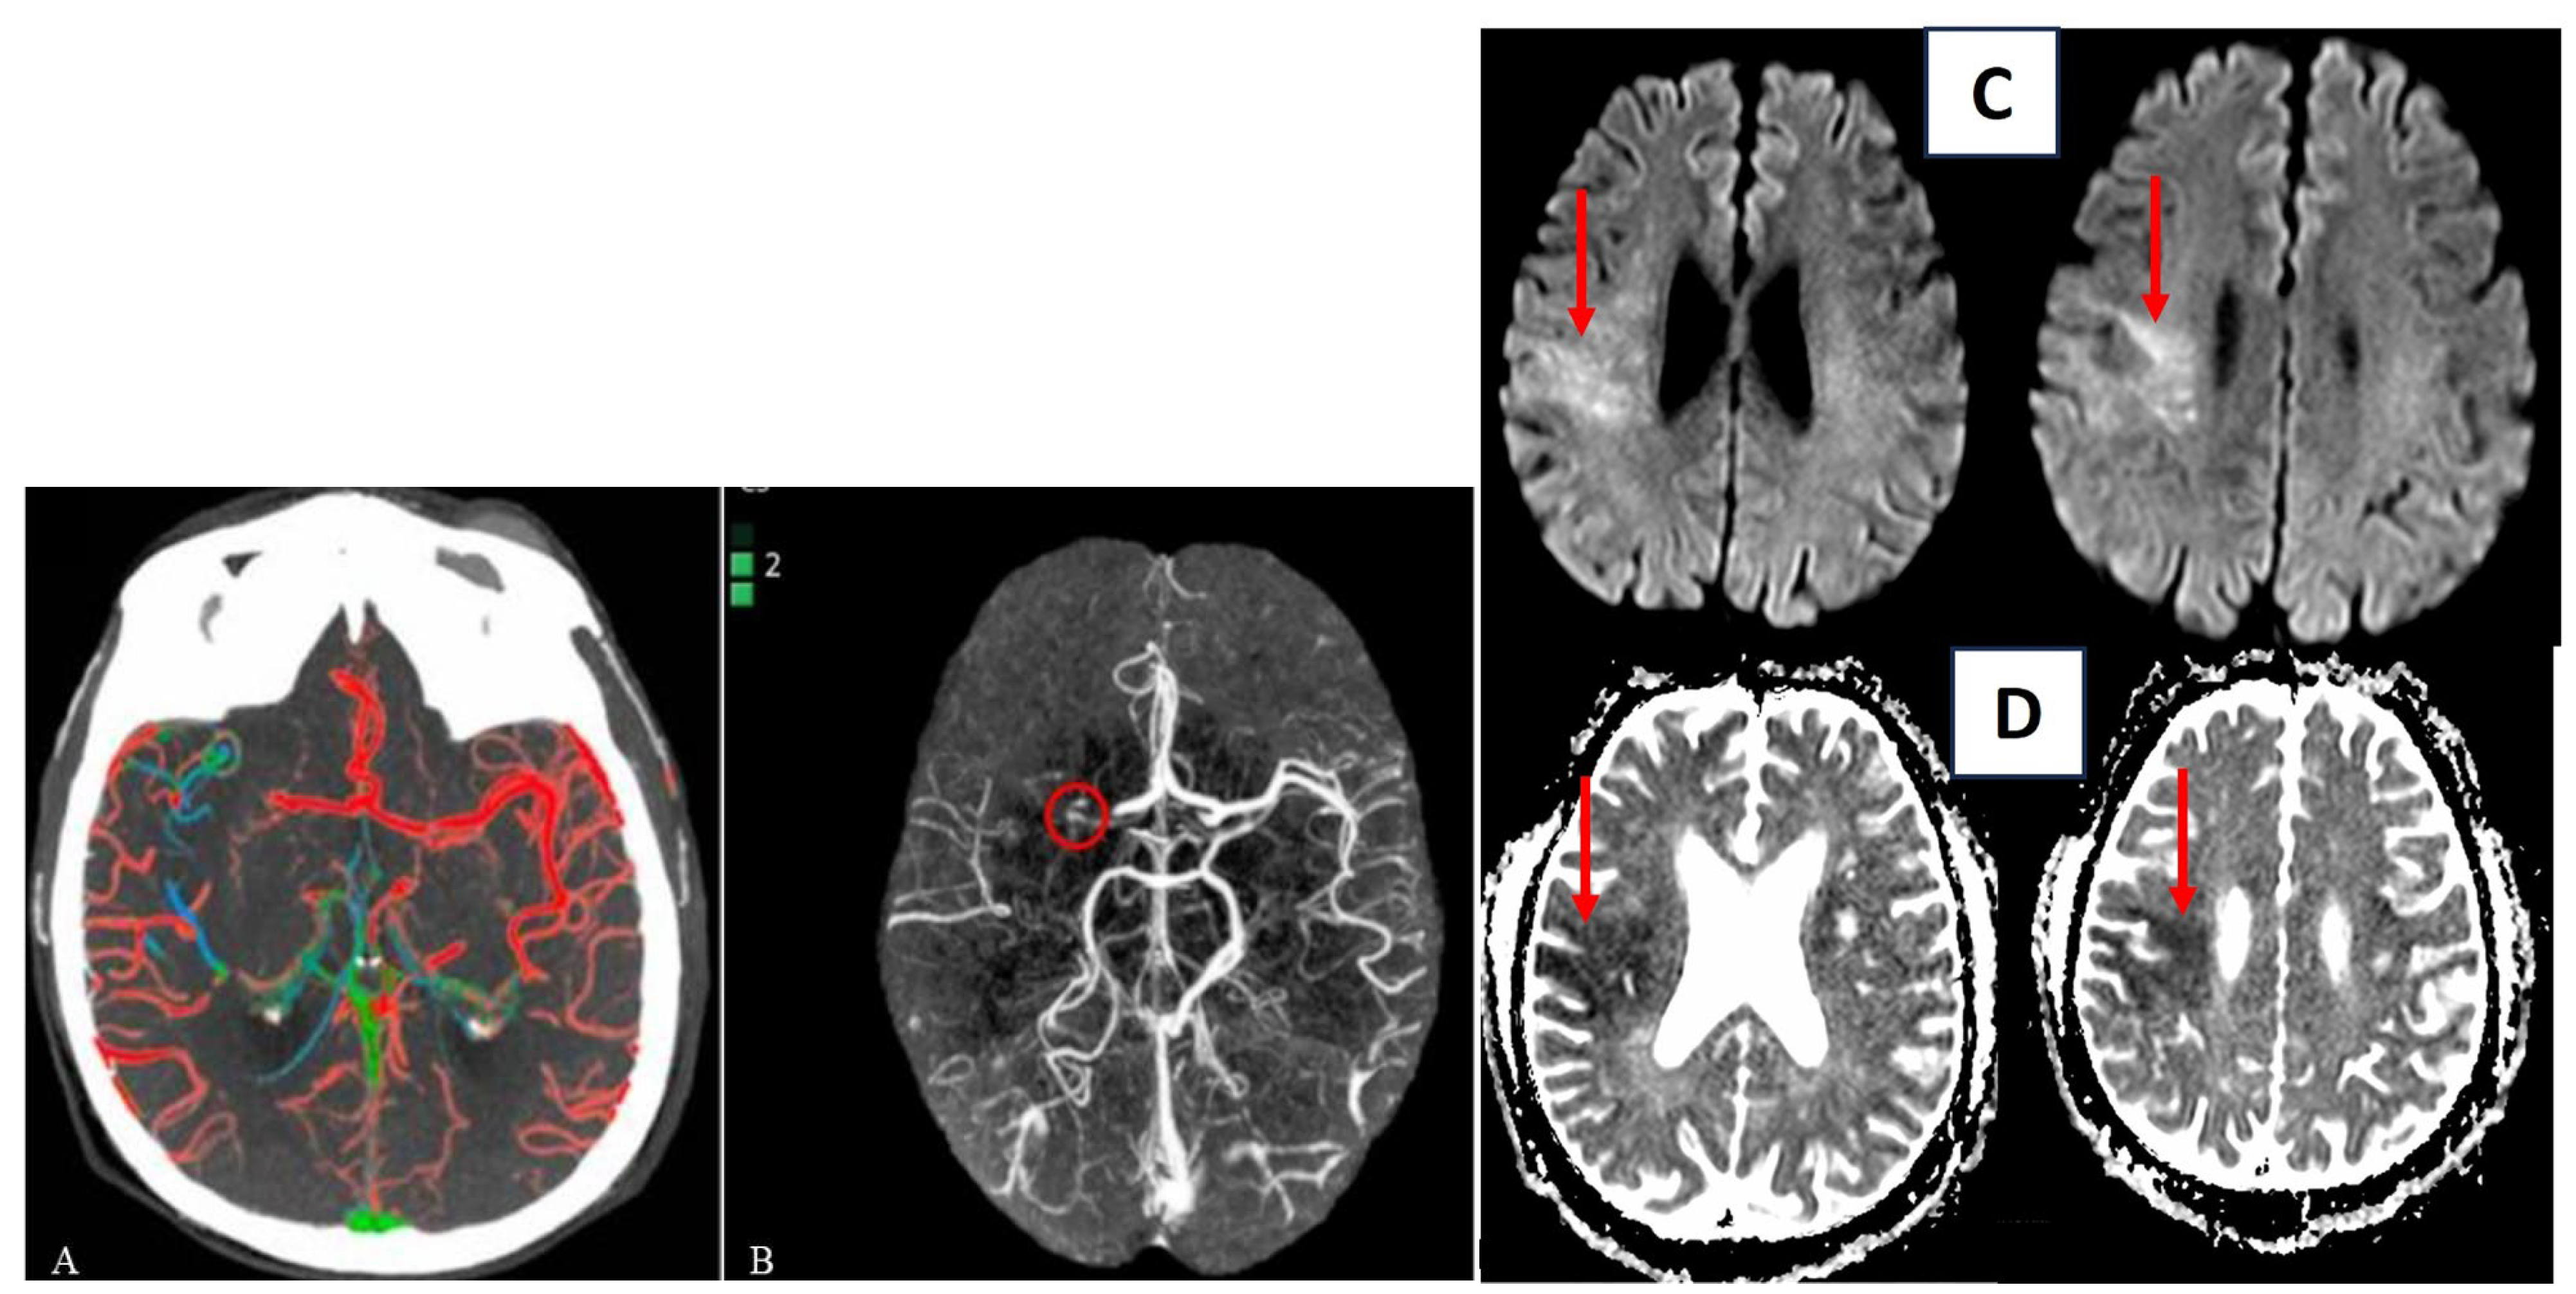

3. Imaging

3.1. Manual Assessment

3.2. Automatic Assessment